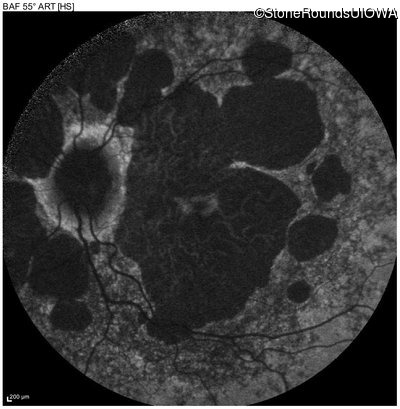

Age at visit: 51 years

OD OS

This 51 year old woman first experienced some abnormality in her distance vision when she was 27 years old. She feels that her vision has been stable since that time.